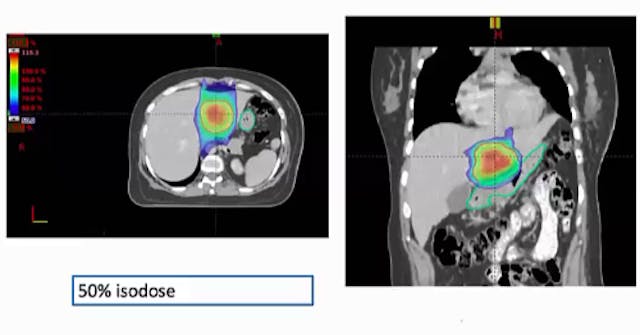

SBRT, motion management, liver metastates, GTV, PTV, isodose, respiration induced motion, diaphragm motion, hysteresis, fluoroscopy, CT scan, 4 DCT scan, USG, FSB (forced shallow breathing), DIBH, DEBH, ABC (active breathing control), ITV, respiratory gating, residual motion, multifocal HCC, moti...